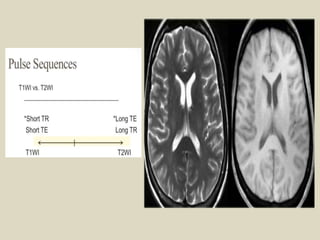

Pulse Sequences.

T1 weighted images

Short TR(300ms-700ms).

Short TE (10ms-30ms).

T2 weighted Images

Long TE(>80ms).

Long TR(>2000ms).

T1WI of the brain is obtained

by short TR and TE.

Images demonstrate good

contrast between soft tissue

types(because different tissues

have different T1 values).

Fat appears bright at the T1WI

and the fluid appears dark.

T1-weighted sequences

provide the best contrast

for para-magnetic contrast

agent(e. g a gadolinium

containing compound.

T2WI of the brain can

be obtained by long

TR(>1000ms) and Long

TE(>60ms).

contrast between normal

tissue and pathology

(because many pathologies

have elevated T2 value due

to increased free water

content).

Fat appears intermediate

to bright at the T2WI and

the fluid appears bright.